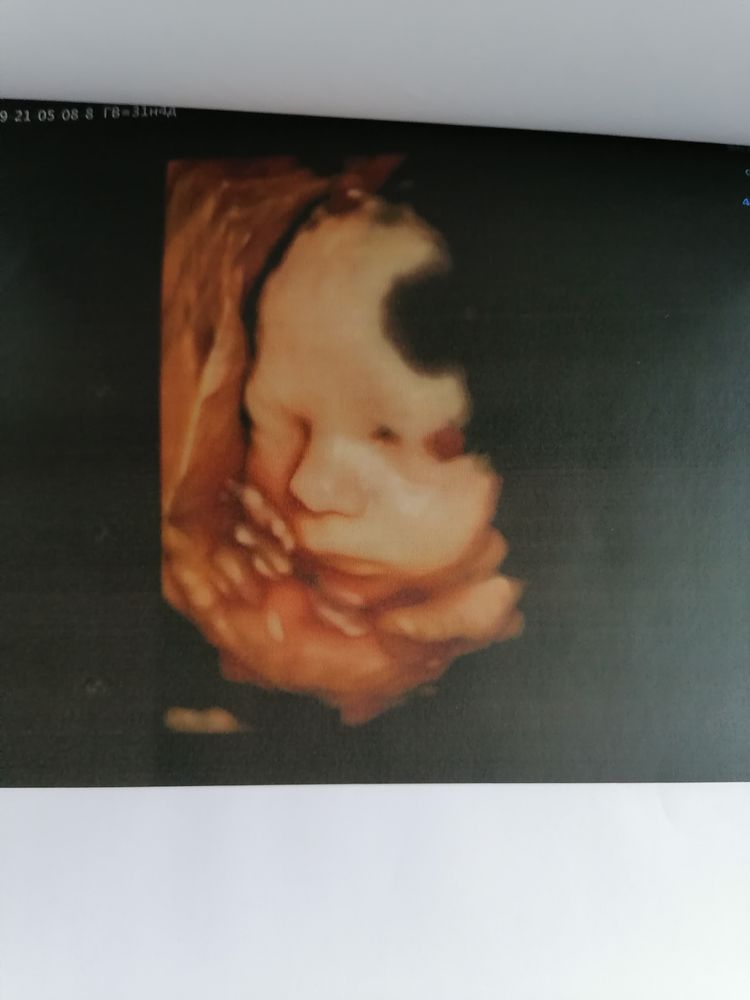

НЮША (ник в ИГ Visla79)

Все замеры делаются в 2D, а в течении УЗИ, если ребенка хорошо видно врач переключает на 3D.

Вот сын в 31 неделю.

НЮША (ник в ИГ Visla79), просто невероятно,уже настоящий человечище!)это конечно отличается от черно-белых фото)